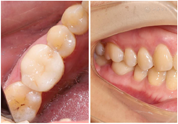

患者既往健康,否认高血压、糖尿病病史,否认外伤手术史,父母均健康,无类似病史。口腔检查:口腔颌面部对称,口腔卫生情况一般,全口牙结石I°,牙龈稍红肿,46

面呈开髓洞型,髓腔暴露,探及远中髓室底穿孔区(图1),面积约为4mm×3mm,穿髓孔区域探痛(+),叩(+),冷热刺激无反应,未探及牙周袋,患牙无松动。根尖片示:46